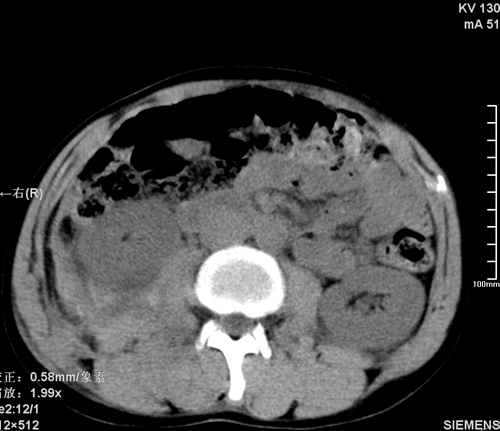

以下是引用qiushi在2008-3-28 12:00:00的发言:[br]腹膜后血肿,所见腰椎横突骨折.[br]建议上传骨窗、腰椎扫描.

以下是引用tao772在2008-3-28 12:29:00的发言:[br]右侧腹膜后积血,右侧腰大肌挫伤,右侧部分横突骨折. 肾脏最好报一下挫伤,必要时增强。